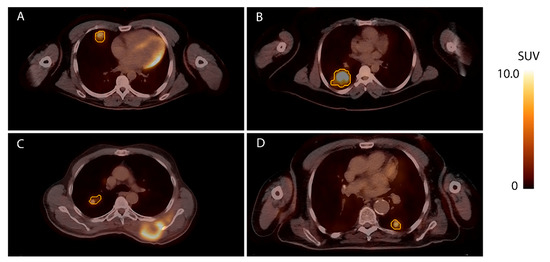

2.3. [18F]FDG-PET/CT

2.4. [18F]]FDG-PET Features